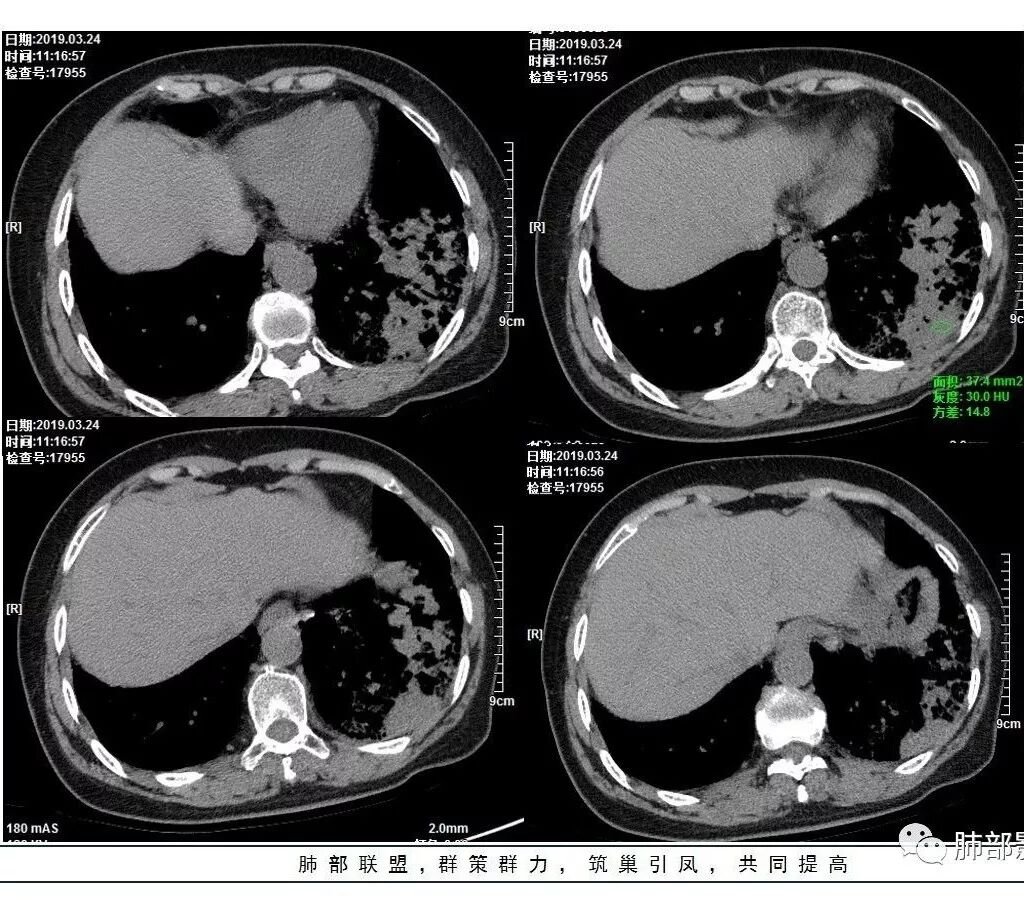

这是老问题:1、肺门区软组织密度影较弥漫;我们常规鉴别的就是结核?鳞癌?既往我们群里基本这两方向。2、弥漫的淋巴结钙化,加上马赛克灌注。马赛克灌注的原因是两个,一个是肺动脉的,一个就是小气道的问题。我们看增强的区域,没有看到栓塞,所以我倾向于小气道的问题,就是弥漫气道病变,慢性气道病变要考虑。我怀疑有没有淀粉样变性累及气道壁改变的可能。淀粉样变性是一个继发性病变,结核也可以,粉尘也可以。

这个病例支气管狭窄后扩张,肺门区有很多钙化的淋巴结,两肺弥漫的马赛克灌注,肺门淋巴结这么多,一个结核,一个尘肺,然后就是一个淀粉样变性,这几种最常见。鳞癌因为老年女性,除非吸烟,不太考虑,又不能绝对排除,所以就把鳞癌放到后。

实变部分强化很明显,怎么解释合理呢

结核强化可以这样吗?

肉芽肿期强化明显

肉芽肿是一个病理的概念,是炎症后期的修复,它的本质其实是迟发型过敏反应引起的炎症,在免疫应答中主要是一些巨噬细胞、上皮细胞来起作用,但是里面有非常丰富的毛细血管,所以这类病变强化很明显,影像上一般是结节状、团块状、大片状,整体有膨隆,边缘也有收缩,肉芽肿是一大类,影像有时很难区分,尘肺、结节病、淋巴瘤样肉芽肿都可以。常见的是炎性的,多见于结核,细菌性感染后期引起的类似op样,影像统称肉芽肿类病变,鉴别炎性还是恶性,要根据边缘、形态、周围结构及内部坏死情况。

今天这个病例有个明显的支气管狭窄,我倾向炎性,主要是和钙化淋巴结相关的,可能是继发的淀粉样变性。到底是什么感染,结核还是其他。我想看看复查后这个淋巴结,有没有突入到支气管腔内,如果有,他是继发于炎症的(比如中叶综合征,就是周围淋巴结压迫支气管,因为钙化淋巴结比较硬,支气管壁扛不住压力,突入支气管腔内,导致管腔狭窄,我们也称为结石征),如果没有,就和淋巴结关系不密切。之前有一例淀粉样变性的,淋巴结弥漫钙化,一种罕见的浆细胞型的CD。